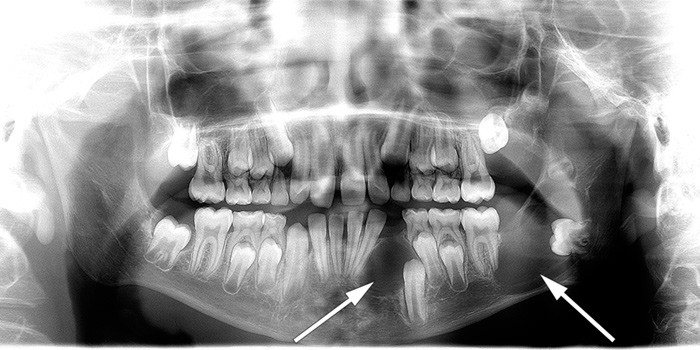

Patients should be monitored periodically for jaw cysts. Such cysts can become large and can displace teeth (6, 8). We recommend that examinations are carried out using a digital orthopantomogram (OPG) (Fig. 2) by a maxillofacial radiologist or dentist who is familiar with performing and interpretating this test. The National Resource Centre for Oral Health in Rare Medical Conditions at Lovisenberg Diakonale Hospital can be contacted for questions relating to the teeth and jaws.

Figure 2  Illustrative image showing jaw cysts. Orthopantomography (OPG) of a boy diagnosed with Gorlin syndrome. In the…

Figure 2 Illustrative image showing jaw cysts. Orthopantomography (OPG) of a boy diagnosed with Gorlin syndrome. In the image mixed dentition can be seen together with two large cystic radiolucencies in the mandible (arrows). Histological examination revealed keratocysts (keratocystic odontogenic tumours). Consent has been given for publication of the image